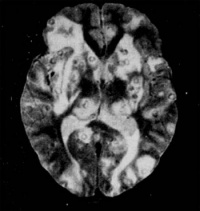

CT:

1.活动期

1)脑实质内脑囊虫大多呈圆形囊性病变,其内头节呈偏心的小点状,附在囊壁上,周围无水肿或轻度水肿,增强扫描囊壁和囊内头节可轻度强化或不强化。

2)脑室内活囊虫以第四脑室多见,呈囊状,表现为脑室扩大积水,其内可见小结节样等或高密度头节,CTM可以显示脑室内充盈缺损。

3)脑沟、脑池、脑裂活囊虫及头节表现与脑实质内活囊虫相似。

2.退变死亡期

1)脑实质内囊虫死亡,头节消失,虫体肿大变形,由于虫体死亡释放大量异体蛋白,在脑实质内引起广泛的低密度脑水肿,有占位效应。增强扫描囊壁明显强化,可呈环状强化或结节状强化,强化环的厚度较囊虫活动期明显增宽。囊内低密度代表囊虫向纤维化和机化过渡。

2)脑室系统内囊虫死亡后,除头节消失,虫体胀大外。囊体增大可引起占位效应。

3.非活动期囊虫死亡后发生钙化,CT呈点状高密度钙化灶。位于蛛网膜下隙者引起蛛网膜肥厚、粘连,可伴有脑积水。

4.混杂期活动期、退变死亡期、非活动期的囊虫混杂存在。

MRI:

可以显示不同时期的囊虫病灶,脑实质内脑囊虫可表现为结节形、环形或囊形,有时可显示头节,增强扫描可强化,有不同程度的脑水肿。脑室内活囊虫特别是在矢状面和冠状面上,T1加权像上囊虫呈低信号,比脑脊液信号略高,其囊壁呈高信号,头节也呈高信号。MRI对钙化的显示不如CT。